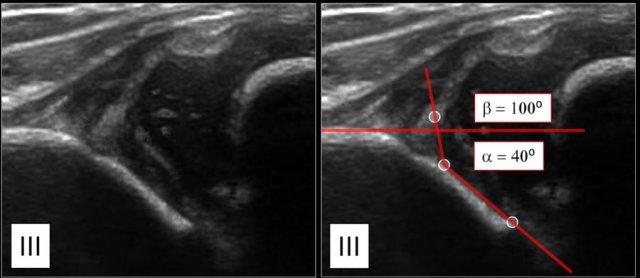

Type III

Ở hông loại III, chỏm xương đùi bị trật khớp.

Sụn viền được di chuyển lên trên.